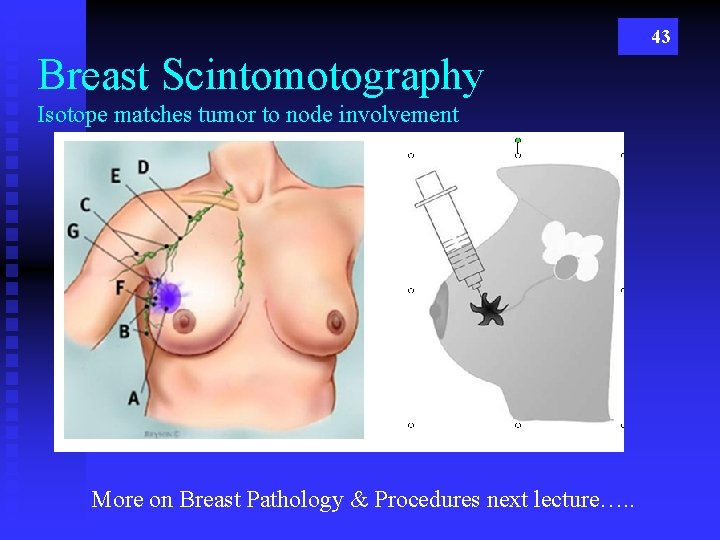

43 Breast Scintomotography Isotope matches tumor to node involvement More on Breast Pathology & Procedures next lecture…. .